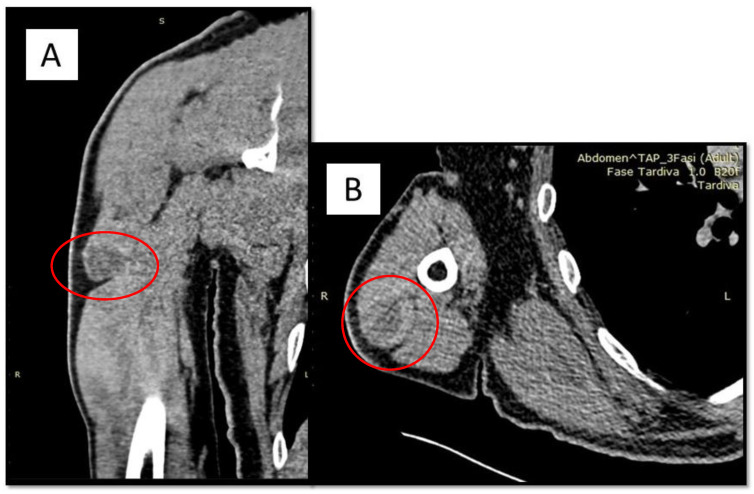

血管瘤样纤维组织细胞瘤(Angiomatoid fibrous histotiocytoma, AFH)是Enzinger于1979年首次描述的一种罕见肿瘤,世界卫生组织(World Health Organization) 2020年将其分类为中级恶性潜在肿瘤。它主要发生在皮下,其特征是不同比例的上皮样细胞、卵形细胞和梭形细胞以结节和合胞生长方式生长,并伴有一些出血性假血管间隙。在本文中,我们报告了一名62岁男性的临床病例,他在右臂出现AFH,并在第一次手术切除三年后复发。三年后,患者出现AFH肌肉内定位,12个月后,诊断为AFH肺转移。考虑到AFH传播的罕见性,我们进行了荧光原位杂交(FISH),我们检测了EWSR1::CREB1基因融合。

Angiomatoid fibrous histiocytoma (AFH) is a rare neoplasm described for the first time by Enzinger in 1979, and classified by World Health Organization 2020 as intermediate malignant potential neoplasm. It mostly occurs in the subcutis and is characterized by varying proportions of epithelioid, ovoid and spindle cells in a nodular and syncytial growth pattern, with some hemorrhagic pseudovascular spaces. In this paper, we report the clinical case of a 62-year-old man who presented with AFH on the right arm, and relapsed three years after first surgical excision. After a further three years, the patient presented with an intramuscular localization of AFH, and 12 months after this, a pulmonary metastasis of AFH was diagnosed. Given the rarity of the spreading of AFH, we performed Fluorescence In Situ Hybridization (FISH) and we detected EWSR1::CREB1 gene fusion.